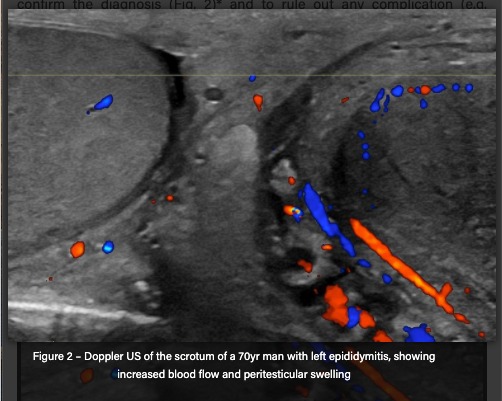

USS can be done of the testes via US doppler to confirm diagnosis if needed or to rule out any complication like testicular abscess.

What will colour US doppler show in epididymitis?

Increased vascularity